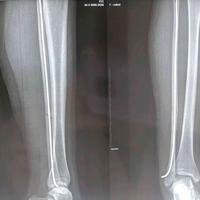

股骨下段及胫骨上段多数平行排列的横行致密

股骨下段及胫骨上段多数平行排列的横行致密线。膝关节外翻畸形。...